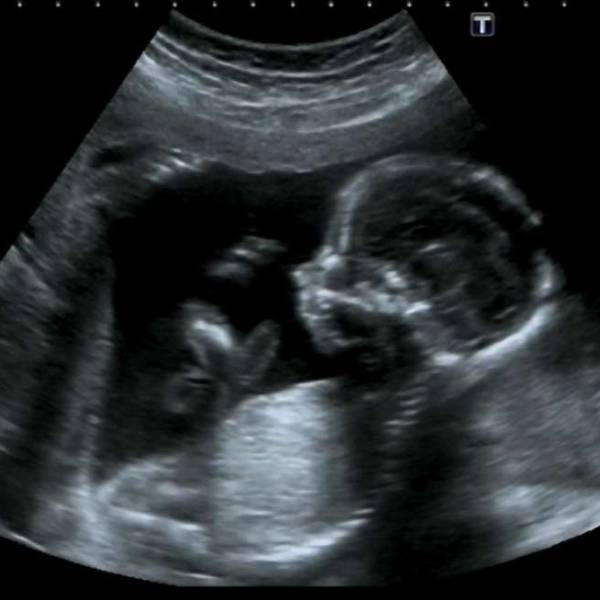

El portal trome.pe señala que uno de los mayores avances en este campo ha sido la Ecografía 7D, que permite registrar imágenes del feto con gran detalle.

Mediante este tipo de ecografía se los puede ver bostezar, sonreír e incluso sacar la lengua.

La Ecografía 7D es la primera que usa la Inteligencia Artificial, destaca el website. Con este mecanismo, el equipo puede ser más intuitivo en la obtención de datos. Por ejemplo, cuando se estudia alguna parte como la cabeza del bebé, el equipo ya está adelantándose y tomando las medidas exactas de la zona, mientras el médico continúa con el diagnóstico.

El nuevo equipo llamado Voluson E10 BT 2020/2021, incluye el software HD Live Studio, que emplea 3 luces móviles e independientes, generando imágenes increíblemente nítidas. Además, las imágenes pueden ser enviadas directamente al teléfono de la mamá o el papá vía email y todo en Súper HD.